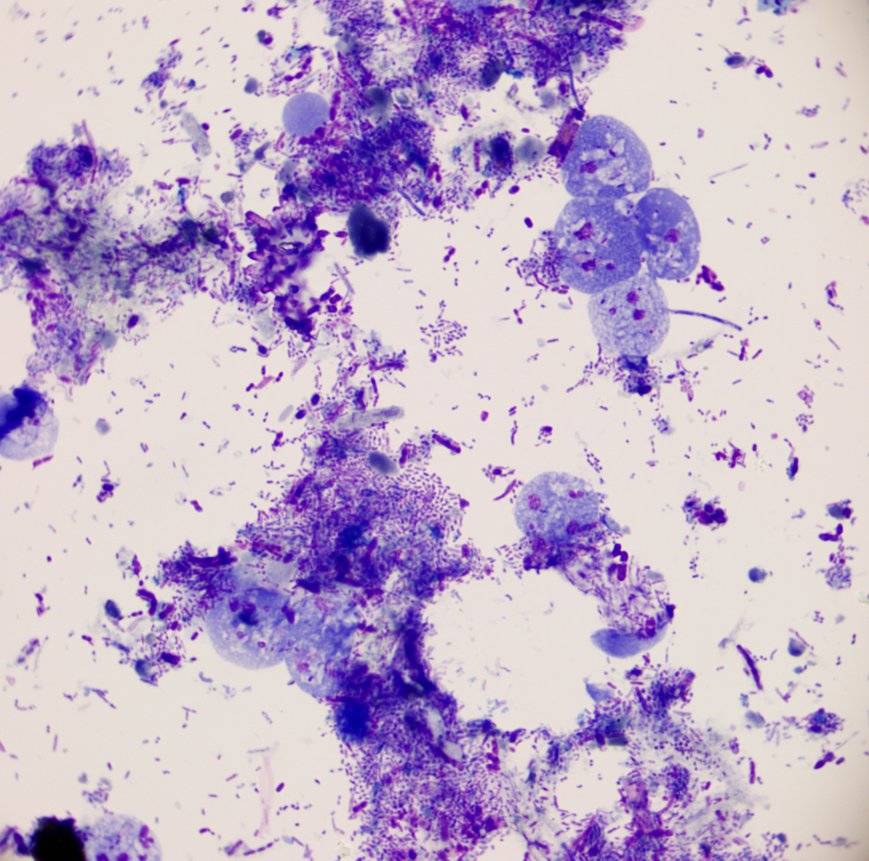

14号 S14 人芽囊原虫的隐秘身姿

人芽囊原虫在常规镜检中易隐匿与白细胞混淆,难以辨识。经瑞氏染色处理后,其类圆形虫体清晰显现,中央大空泡与周缘细胞核的独特结构一目了然,胞浆细节尽数呈现。这抹染色后显露的微观身影,为该虫的精准检出提供了关键依据,尽显镜下染色技术的精妙与微观生命的隐秘之美。

192号 S192 人芽囊原虫

人芽囊原虫中间可见一个较大空泡,外圈似有一圈薄薄的胞质,在胞质边缘有数个“亮点”,此为人芽囊原虫形态,“亮点”为其核。在体外培养时,可有空泡型、颗粒型、阿米巴型、复分裂型、包囊型。